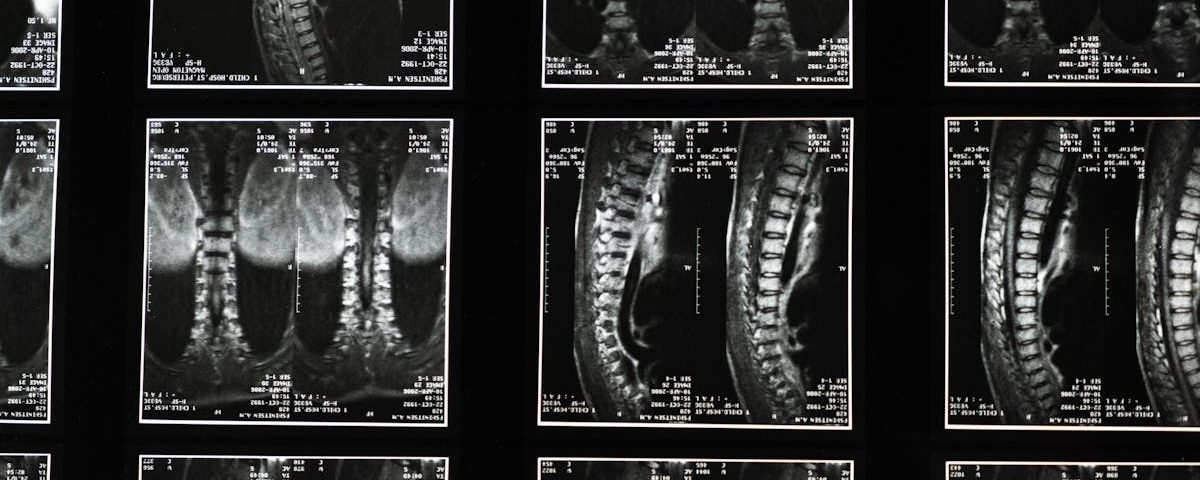

Imagerie 3D – Fournit une visualisation précise des structures vertébrales pour un traitement personnalisé.

Évaluation par imagerie

Utilisation d’images pour guider et évaluer l’efficacité des traitements.